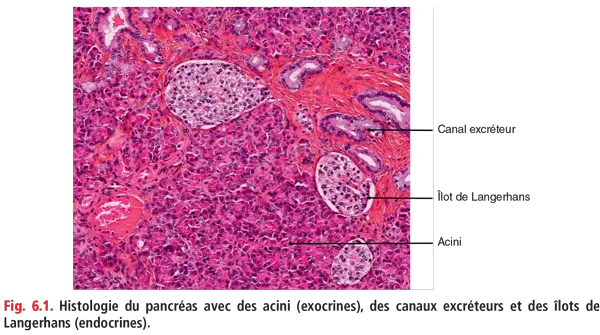

Le pancréas est une glande mixte, endocrine et exocrine (fig. 6.1).

Fig 6.1

Le pancréas exocrine est constitué de cellules acineuses, formant des acini regroupés en lobules, sécrétant les enzymes pancréatiques, drainées par les canaux excréteurs (canaux intralobulaires, puis interlobulaires et canaux collecteurs, jusqu’au canal de Wirsung). Le canal de Wirsung est également appelé conduit pancréatique principal tandis que les autres canaux correspondent aux conduits pancréatiques secondaires.

Le pancréas endocrine est représenté par les îlots de Langerhans, dispersés au sein des lobules pancréatiques. Ces îlots sont constitués de différents types de cellules qui se distinguent par l’hormone qu’elles sécrètent (insuline, glucagon, somatostatine, polypeptide pancréatique).